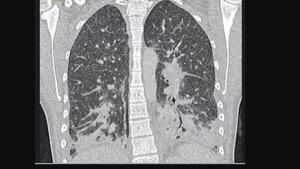

• بعد مرور 9 شهور: تقوم رئتا المدخن بإصلاح نفسها، وتعمل الأهداب الآن بكامل طاقتها.